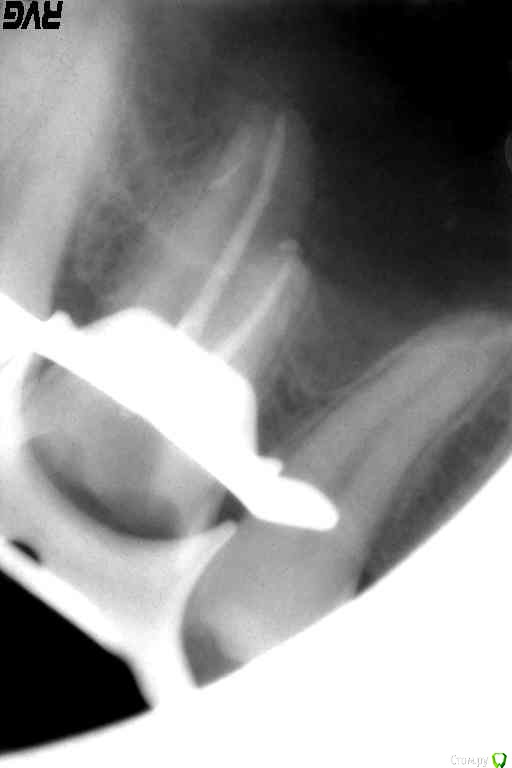

Др.Косякович Опубликовано 6 марта, 2016 Поделиться Опубликовано 6 марта, 2016 Добрый день уважаемые коллеги. Очень нужен Ваш совет.Обратилась пациентка с пульпитными болями в зуба 1.6. с двумя каналами( нёбным и мезиальным) разобрался, а вот в дистальном беда-бедища. До апекса сразу пилотным файлом не добрался и расширят его ручными примерами и протейперами, мыл гипохлоритом. И вот наконец белый ример ушёл чуть глубже. Да там и остался. Тогда, дай думаю ультразвуком отзвучу гипохлорит в нём и запломбирую. И тут белый файл эндочака провалился чуть глубже и из канала пошёл эксудат. Каналы помыл, дистальный закрыл пином, а небный и мезиальный запломбировал гуттаперчей. Потом в мезиальном оставил каласепт на 2 недели и временная пломба витребонд. Как быть с этим каналом. чем его плоомбировать и каковы по Вашему мнению прогнозы? Ссылка на комментарий

Др.Косякович Опубликовано 8 марта, 2016 Автор Поделиться Опубликовано 8 марта, 2016 Да так и есть, пин поставил, пока каналы пломбировал, чтоб не подтекало. А потом вместо пина оставил в канале каласепт на две недели. Ссылка на комментарий

Др.Косякович Опубликовано 8 марта, 2016 Автор Поделиться Опубликовано 8 марта, 2016 Изучая форум, я понял, что при перфорациях их закрывают ста или триоксидентом. А в моём случае он показан? Ссылка на комментарий

Доктор Дмитрий Опубликовано 8 марта, 2016 Поделиться Опубликовано 8 марта, 2016 Изучая форум, я понял, что при перфорациях их закрывают ста или триоксидентом. А в моём случае он показан?Да, апикальные 2-3 мм Ссылка на комментарий

Др.Косякович Опубликовано 9 марта, 2016 Автор Поделиться Опубликовано 9 марта, 2016 То есть образно говоря можно замуровать там обломок? Ссылка на комментарий

тимован Опубликовано 17 марта, 2016 Поделиться Опубликовано 17 марта, 2016 такой обломок можно замуровать. главное не пытаться вытаскивать. Ссылка на комментарий